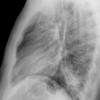

Case 2  Lingular pneum Lat

Date: 04/17/2005

Views: 7025